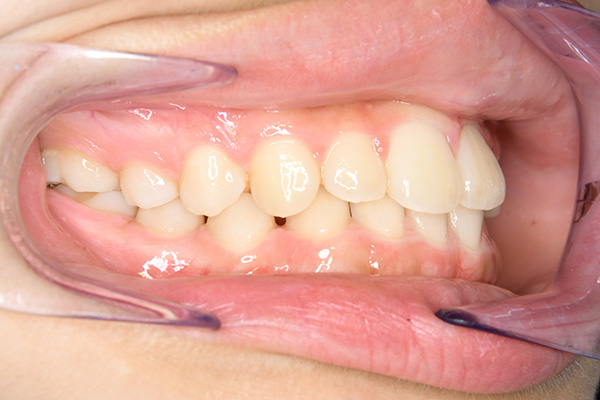

動的治療開始前(9歳7ヵ月)

動的治療開始前

(9歳7ヵ月)

口腔内所見 over jet -2.5mm、over bite 2.0mm、大臼歯関係はⅠ級 。Hellmanのdental ageはⅡCであり前歯部は反対咬合を呈していた。